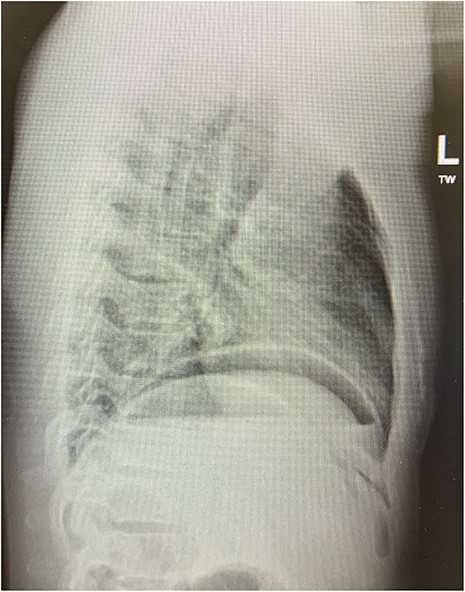

The patient was transferred to the surgical ward for ongoing cares, remaining nil by mouth and commenced on intravenous antibiotics and proton pump inhibitor infusion. On post-operative day 3, a follow-through contrast study showed no leak of enteric contents from the stomach (Fig. 3) with transit of the contrast into the duodenum, and a concurrent ileus was shown with prominent small bowel loops (Fig. 4). A clear fluid diet was initiated, with gradual upgrade before discharge to usual residence and follow-up gastroscopy as outpatient.